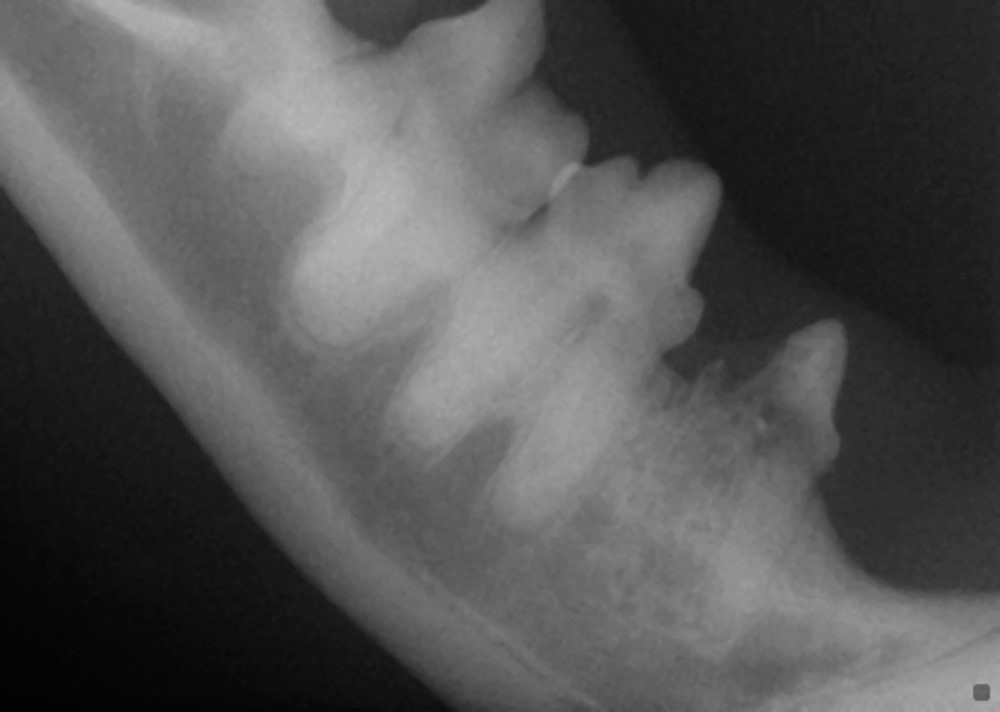

Cat Teeth Xray . 50k views 13 years ago. Superimposition of the nasal ridge of the incisive bone over the incisor roots has been. Becoming familar with the techniques required for dental radiology and radiography can, therefore, be greatly beneficial. Retained tooth root fragments in dogs and cats are a common radiographic finding. Information crucial to the diagnosis and treatment of feline oral diseases can be ascertained using dental radiography and the inclusion of this technology has been shown to be the best way to improve a dental practice. The dotted lines show the trajectory of the zygomatic arches on both radiographs, illustrating how more superimposition with structures of interest occurs in the intraoral view than in. Sign up for my monthly newsletter at:. 6,7 tooth roots may be retained as a result of poor extraction technique or may be fractured as a result of trauma or tooth resorption.

Interpretation of Dental Radiographs in Dogs and Cats, Part 2 Normal Cat Teeth Xray 6,7 tooth roots may be retained as a result of poor extraction technique or may be fractured as a result of trauma or tooth resorption. Superimposition of the nasal ridge of the incisive bone over the incisor roots has been. Retained tooth root fragments in dogs and cats are a common radiographic finding. Becoming familar with the techniques required for. Cat Teeth Xray.

Interpretation of Dental Radiographs in Dogs and Cats, Part 1 Cat Teeth Xray 50k views 13 years ago. Superimposition of the nasal ridge of the incisive bone over the incisor roots has been. The dotted lines show the trajectory of the zygomatic arches on both radiographs, illustrating how more superimposition with structures of interest occurs in the intraoral view than in. 6,7 tooth roots may be retained as a result of poor extraction. Cat Teeth Xray.

Interpretation of Dental Radiographs in Dogs and Cats, Part 2 Normal Cat Teeth Xray Information crucial to the diagnosis and treatment of feline oral diseases can be ascertained using dental radiography and the inclusion of this technology has been shown to be the best way to improve a dental practice. 6,7 tooth roots may be retained as a result of poor extraction technique or may be fractured as a result of trauma or tooth. Cat Teeth Xray.